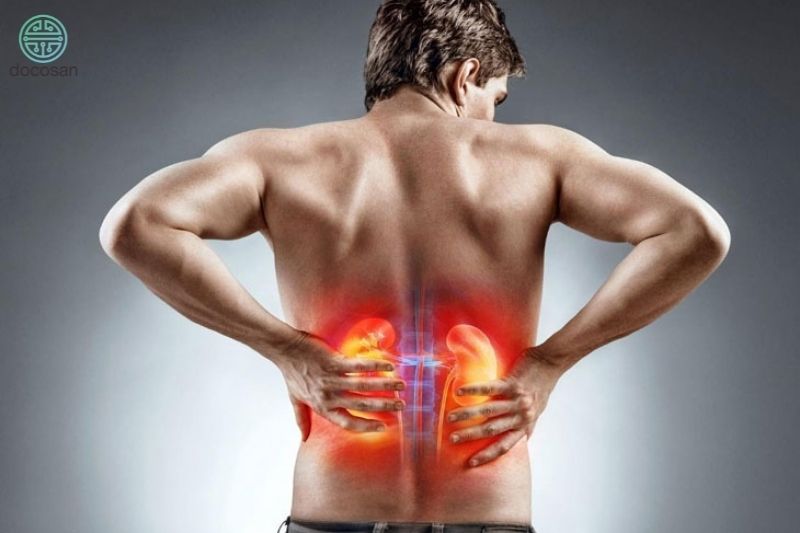

Triệu chứng của thận ứ nước độ 4

Biểu hiện của thận ứ nước thay đổi tùy vào mức độ ứ nước, thời gian khởi phát và nguyên nhân gây nên tình trạng ứ nước của thận. Những trường hợp nặng như thận ứ nước độ 3 và 4 thường có biểu hiện rầm rộ hơn nhiều so với các mức độ trước đó. Một số biểu hiện của thận ứ nước độ 4 có thể gặp ở người bệnh như:

- Thường xuyên xuất hiện các cơn đau liên tục, tăng dần, kéo dài từ 30 phút đến 4-5 tiếng, có thể âm ỉ suốt cả ngày, đau thường khởi phát ở vùng mạng sườn hay hông lưng rồi lan xuống và ra sau. Người bị thận ứ nước mạn tính thường đau âm ỉ vùng hông lưng làm ảnh hưởng đên đời sống sinh hoạt hằng ngày. Hoặc đôi khi các trường hợp thạn ứ nước mạn tính lại không xuất hiện các biểu hiện đau đáng kể.

- Khung xương chậu căng tức do đài bể thận dãn ra dẫn đến phải chịu một trọng lượng quá tải, đôi khi bệnh nhân có thể sờ thấy một khối rõ ở vùng hông lưng. Khi vỡ có thể dẫn đến cơn đau dữ dội, đột ngột, đau lan khắp bụng.